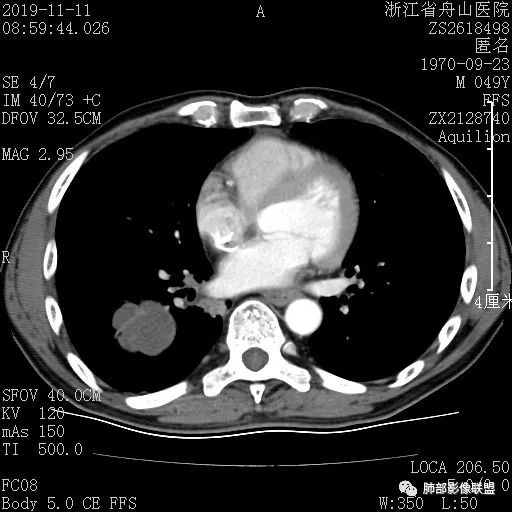

case3

男 29

开始讨论

Clover:

原位伴肺泡塌陷

王秀仙: 医学百科网 | YxBaike.Com

右肺下叶磨玻璃结节,边缘清晰,中央肺泡塌陷,ais 医学百科网 | YxBaike.Com

错过: 医学百科网 | YxBaike.Com

PGG0,为AlS

管洪林:

右肺下叶血管旁混合磨玻璃,实性边界清晰,考虑AIS伴有肺泡塌陷。

这个病灶大小是多少,比例尺一格是1cm吗?

心灵鸡汤: 医学百科网 | YxBaike.Com

是的CT值可以参考下 大小也没有

CT值未见,有点可惜,确实需要分区测值 医学百科网 | YxBaike.Com

没拷太多图,大小只能眼观

MIA并肺泡塌陷或者AIS,大小目测大于6mm 医学百科网 | YxBaike.Com

应该是小于1CM,目测

AIS或MIA并肺泡塌陷 医学百科网 | YxBaike.Com

病理诊断 : 医学百科网 | YxBaike.Com

MIA

我觉得有中央肺泡塌陷,是比较轻的MIA 没看病理切片 肯定有塌陷 医学百科网 | YxBaike.Com

这个病例在影像如何下结论合适呢,如何建议

小的实性区边界清楚 医学百科网 | YxBaike.Com

这个除了CT值,其他的没有MIA的征象了 ,这个需要CT值精确判断

感觉密度略偏高,血管进入略增粗 医学百科网 | YxBaike.Com

所以我首先还是考虑MIA

肺泡塌陷可以见于ais和mia?iac可以吗? 医学百科网 | YxBaike.Com

都可以 医学百科网 | YxBaike.Com

一句话小结: 医学百科网 | YxBaike.Com

血管旁磨玻璃小结节影,边界如此清晰,足以使人高度警惕! 医学百科网 | YxBaike.Com

中央显示有较清楚结节样实性密度区至少应想到微浸润腺癌的可能性。